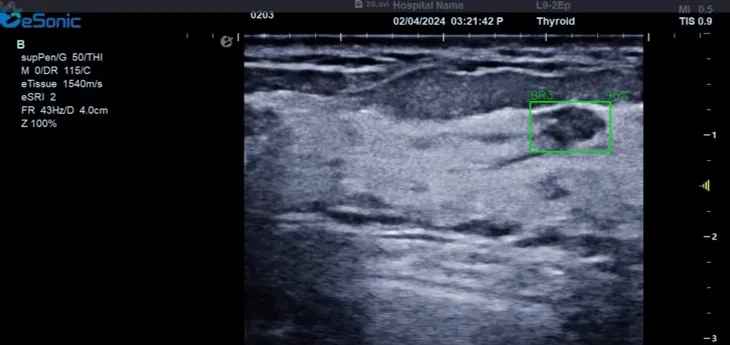

3377体育医疗(ESI)表示,其最新的人工智能功能可以帮助到医疗机构的工作效率,功能包括,实时、动态、快速自动识别病灶,良恶性病灶概率预测,甲状腺结节和乳腺的二维灰阶动态自动实时检测需求,提供多个结节动态检测轮廓框。实时获取多幅具备临床特征(大小、属性等)的结节切面,同时提供当前切面所示结节的结节大小、属性特征、TI-RADS 分级。

对于甲状腺结节相关的自动检测功能,甲状腺结节病灶检出率≥95%,良恶性分类灵敏度≥90%、良恶性分类特异度≥85%。